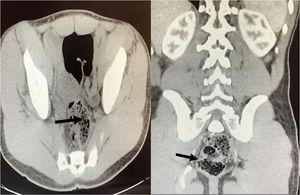

Se repite ecografía abdominal objetivándose ambos riñones con aparente discreto engrosamiento cortical difuso y ligera ectasia calicial bilateral simétrica, vejiga replecionada con ecos internos en relación con la presencia de contenido (detritus y fibrina). Se decide completar estudio con Uro-TAC (fig. 1), con hallazgos sugestivos de esquistosomiasis urinaria. Se realiza estudio parasitológico en orina observando: abundantes huevos de S. haematobium. Así mimo, en el estudio parasitológico se detectan huevos de T. trichuria y N. americanus en heces. Es derivado a consulta de Medicina Interna, instaurándose tratamiento con albendazol y praziquantel, con estudios parasitológicos subsecuentes negativos; actualmente a seguimiento en vista de viajes frecuentes a Madagascar y Mozambique.